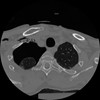

12 P.BLANDAS,,Vol,0.5,P.BLANDAS,,